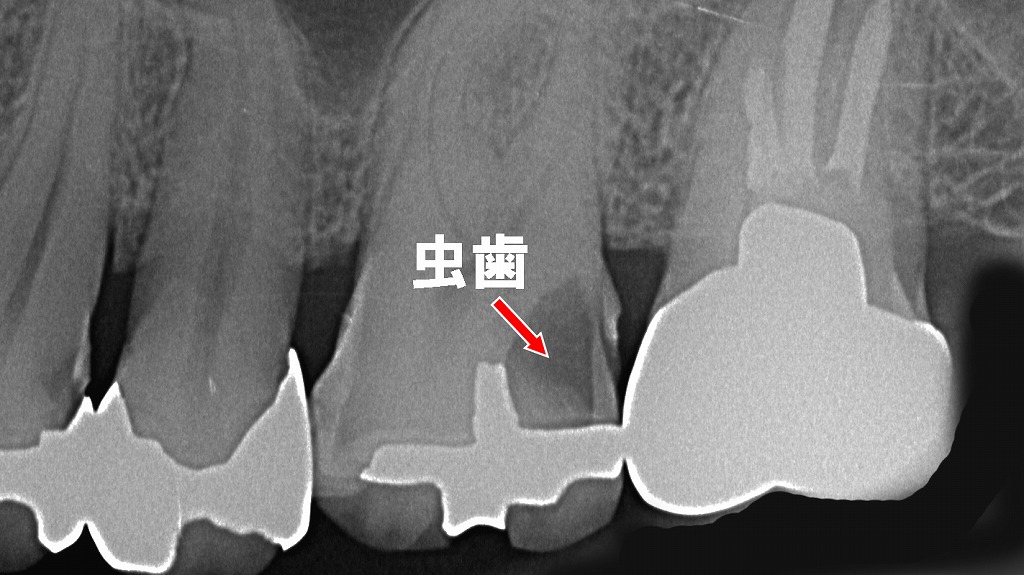

銀歯(メタルインレー)は経年劣化により接着剤が緩み、歯と銀歯の境界にわずかなすき間が生じることがあります。この隙間は外側から見えにくく、プラークや細菌が侵入すると“二次う蝕(すき間むし歯)”として内部で進行します。

画像では、銀歯の下に形成された虫歯が明瞭に確認でき、長年使用した補綴物には定期的なチェックが必要であることを示しています。